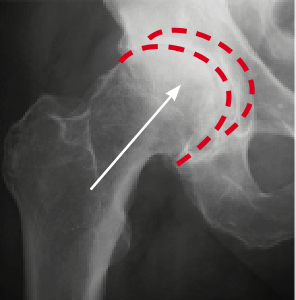

Na slici lijevo (snimljenoj prije tretmana) vidljiv je nedostatak sinovijalne tekućine, što uzrokuje trošenje kostiju. Na slici desno, zahvaljujući tretmanu, kosti se kreću glatko i bezbolno. Struktura sinovijalne tekućine se obnovila – vratila je svoja svojstva podmazivanja.

Prof. Zygler je dokazao (što potvrđuju rendgenske i ultrazvučne snimke) da njegova formula protiv artritisa potiče obnovu zglobova na tri ključna načina:

Već nakon 4-5 tjedana Zyglerovog tretmana, zglobna hrskavica će se iz tanke i ispucane pretvoriti u debelu i elastičnu. Zahvaljujući tome, smanjit će se trenje u zglobovima, a svaki pokret ćete izvoditi sigurno i s lakoćom.